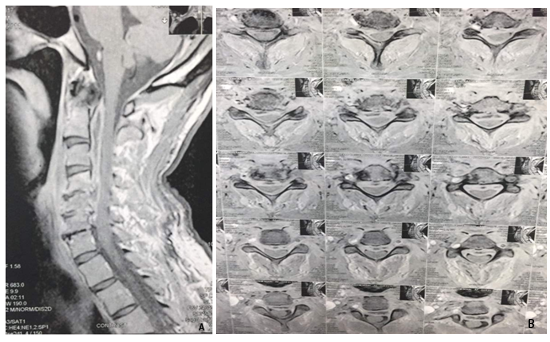

56 year old male from Rosetta complained of acute onset of neck pain for about 2 months with progressive course of upper limbs weakness with no sphincter affection. No previous dental nor neck nor back surgery nor acupuncture. History of renal impairment and on medical treatment for about 4 years. Body temperature was about 38.2 C. Physical examination showed marked mid neck tenderness, no palpable masses were felt, no lymph nodes were felt. Neurological examination revealed grade 3 paraparesis in the upper limbs while grade zero in both lower limbs on Medical Research Council (MRC) scale. Preservation of the deep sensation while loss of the superficial sensation, positive Hoffman sign and positive planter reflex. Magnetic Resonance imaging of the cervical spine showing ventral cervical spinal cord compression by an epidural abscess extending from the apex of dens to the level of C5. Decreased spinal canal diameter and mild spinal cord compression were present (Figure 1).

Figure 1 (A) Preoperative MRI cervical spine contrasted TW1 sagittal view (B) preoperative MRI cervical spine contrasted TW1 axial view. Both are showing ring thick wall enhanced oblonged mass ventral to the cervical spinal cord and extending from apex of C2 till C6 with obliteration of the subarachnoid space.